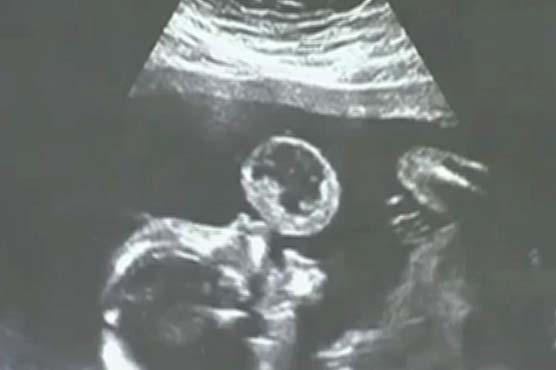

Summary A tumour in the mouth of the baby, while in mother's womb, was removed in the US.

An unborn baby girl in the US was detected with an extremely rare cancerous tumour in the mouth, but doctors successfully removed it in one of the worlds first such surgeries in the womb.Leyna Gonzalez was born healthy five months later.She is now nearly two years old, and the only sign of cancer is a tiny scar on her mouth.Her mother Tammys pregnancy scan at 17 weeks showed Leyna had an aggressive mouth tumour. It looked like the baby was blowing a bubble.Doctors said it was a rare tumour called an oral teratoma, and that there was little chance Leyna would survive.Surgeons used a laser to cut the tumour from Leynas lips after pushing a super-fine needle into Tammys womb for the hour-long operation at the Jackson Memorial Hospital in Florida.Details of the case have been published in US medical journal Obstetrics and Gynaecology.